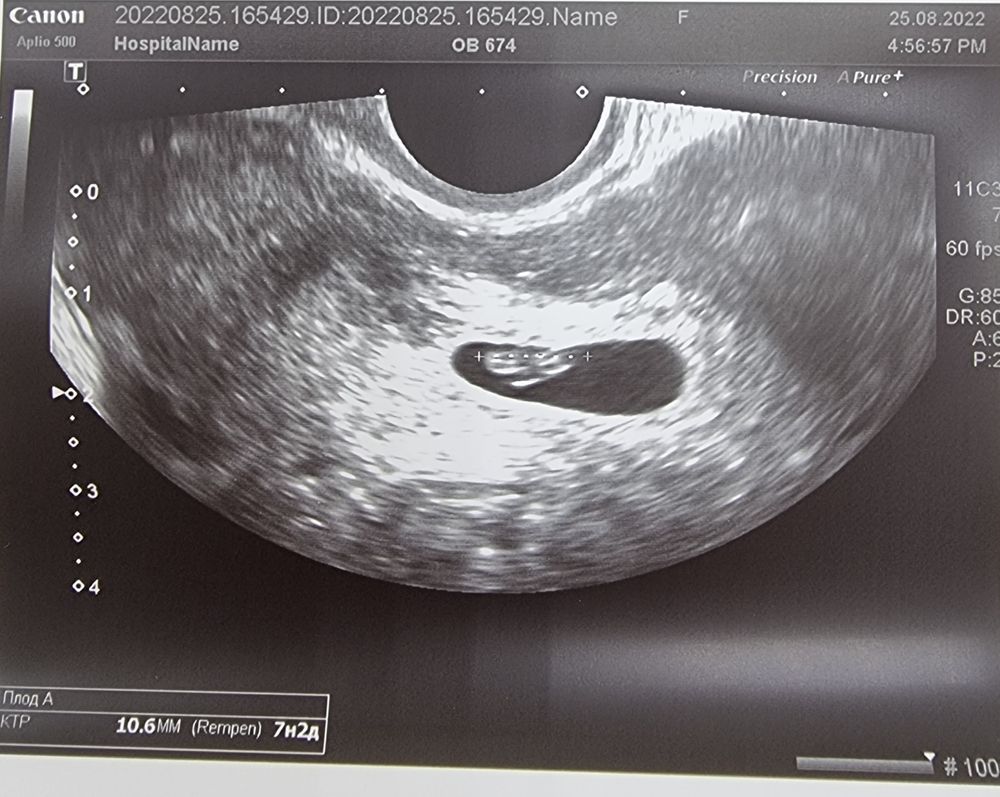

УЗИ, КТГ, доплерЯ все ещё за городом, сегодня выбрались в ближайший город и я сходила на узи. Из хороших новостей: эмбрион на месте, ктр 10,6мм, сердцебиение есть! По узи срок 7+2.

Из не очень хороших: есть 2 гематомы, одна 15х9мм, вторая 15х7мм. Узист написала "свежие", хотя алых выделений не было и нет странно...